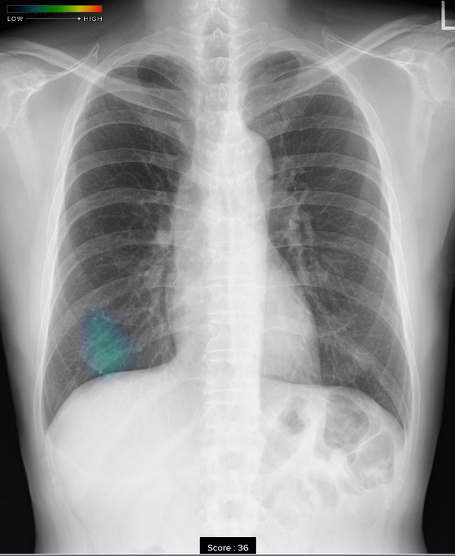

当院では、胸部X線画像病変検出ソフトウェア(富士フィルムメディカル製)を導入しています。

AIによる診断補助が可能となり、今まで以上に質の高い診断を行うことができるようになりました。